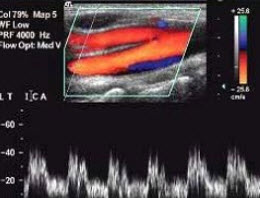

14、单项选择题 女性腹腔最低部位是()

该图蓝色血流信号表示()

A.动脉血

B.静脉血

C.血流方向背离探头

D.血流方向朝向探头

E.以上均不是